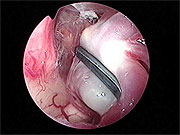

神経内視鏡による同時観察下で顕微鏡手術(図4)。

神経内視鏡は顕微鏡の死角を補い、動脈瘤周囲の細い血管を温存することに非常に有用です(図5、6)。この方法は当科において確立され、現在では動脈瘤手術において実に有用で必要な方法として認められています。